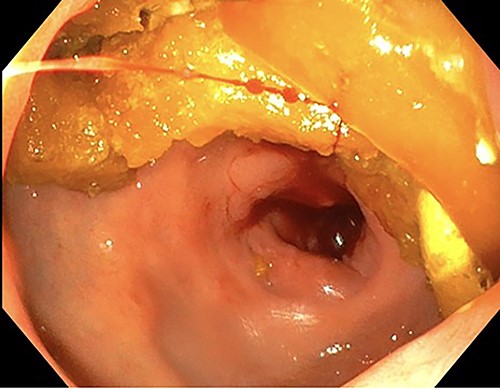

Endoscopic retroflexed view of the stomach showing gastritis, patchy telangiectasia and sloughy mucosa at the incisura.

Endoscopy showing duodenitis with stricture at the second part of duodenum (D2).